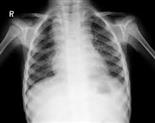

يقصد بالالتهاب الرئوي لدى الأطفال أيّ الذي يصيب النسيج الرئوي، وهو مرض يتميز بالحمى، والسعال، وضيق النفس، وتسرع التنفس، وقد تظهر الإصابة عادة على الصورة الشعاعية للصدر.

صورة الصدر الشعاعية التي تكشف وجود ذات الرئة وتحدد نوعها، كما تحدد الصورة الشعاعية للصدر وجود انخماص رئوي (Atelectasis) أو انصباب جنبي (Pleural effusion).

ومن الجدير بالذكر أن التغيرات الشعاعية لا تتطابق دومًا مع المشاهدات السريرية.